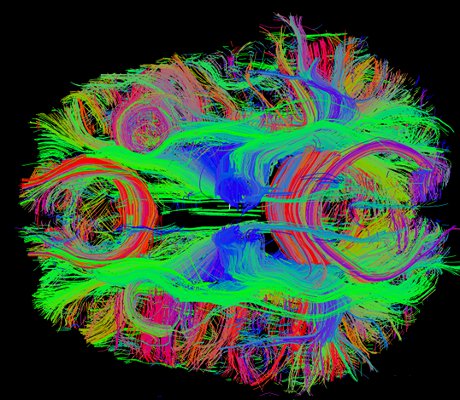

Immagine, Credito: Dominio Pubblico CC0.